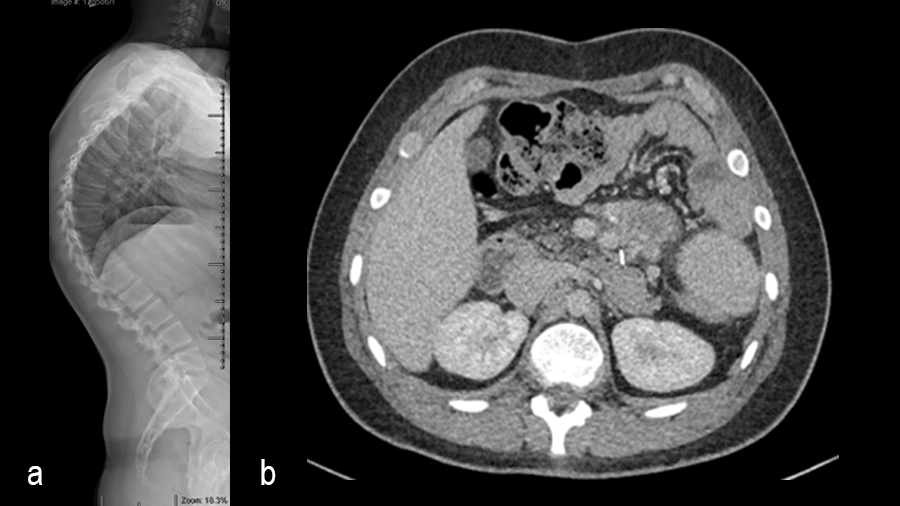

A 19-year-old man with colon cancer was admitted to the spine clinic with pain and progressive kyphosis (Fig 5a). Preoperative CT imaging (Fig 5b) showed a residual mass abutting the superior mesenteric artery.

Surgery was undertaken with TriALTIS™ posterior spinal instrumentation system from T5 – L1 to correct and support the kyphotic deformity (Fig 6a-b). The upper and lower instrumented vertebrae were selected to allow symmetry of fixation above and below the apex of the kyphotic curve. Care was taken not to overcorrect the hyperkyphosis given the abdominal mass abutting the superior mesenteric artery. During surgery, multiple sequential reducers were used to achieve cantilever reduction of the deformity (Fig 7).